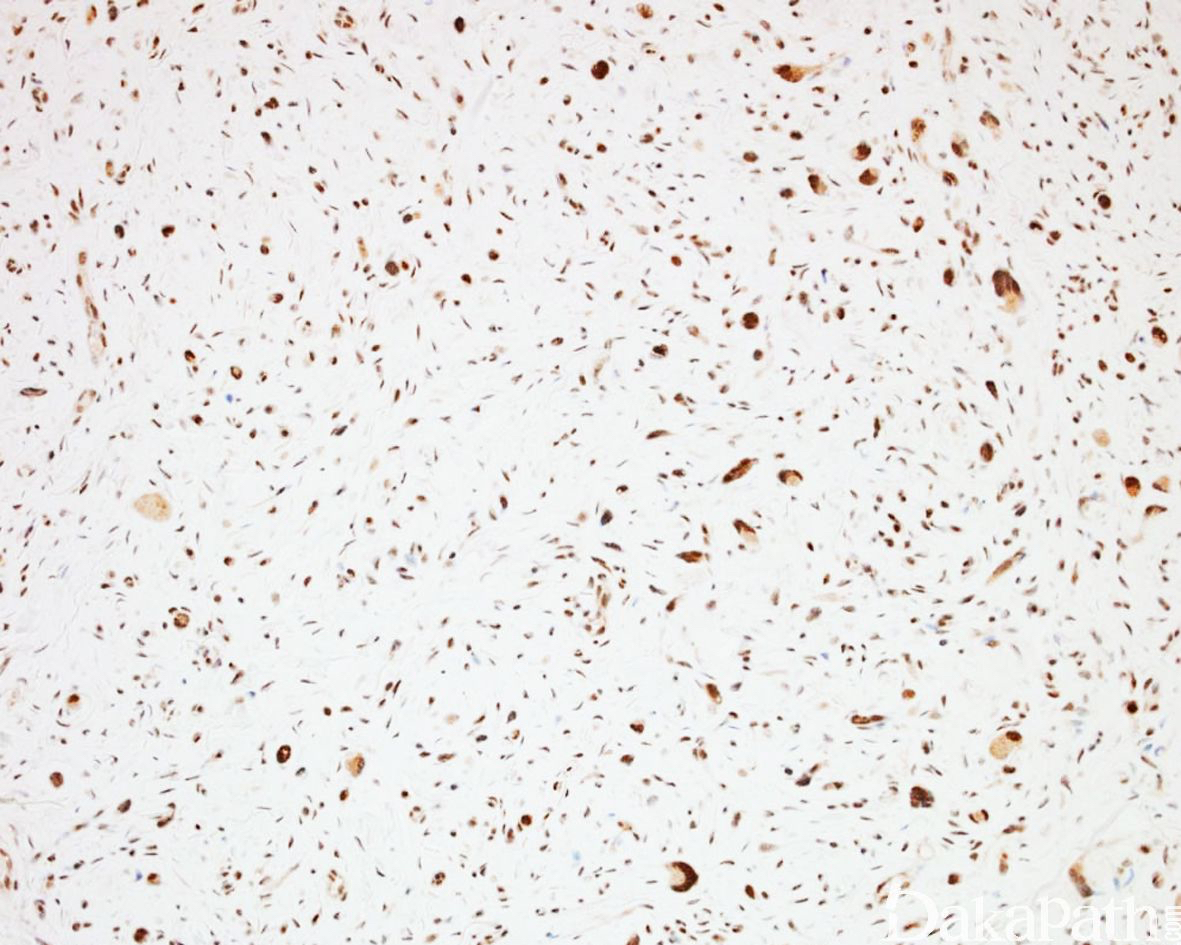

免疫组织化学染色:

S-100. MBP、XIIIa、CD34 阳性,可见 EMA 阳性神经束膜细胞,NF 阳性的轴突成分;P53 阴性,Ki67 增殖指数低,H3K27me3 无表达丢失;多数病例无表达缺失,少数可出现表达缺失。